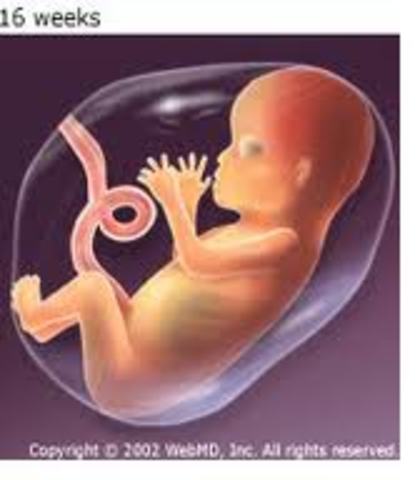

• Month Four

Month Four

Month Four the baby is beginning to gain control of their muscle movements. they can even make facial expressions in response to changes in the uterine environment. \the uterus and skin need twice as much blood as usual, and the kidneys need 25% more blood than usual. the uterus has outgrown the mothers pelvis and will be forced into the abdomen, which will decrease her lung capacity.